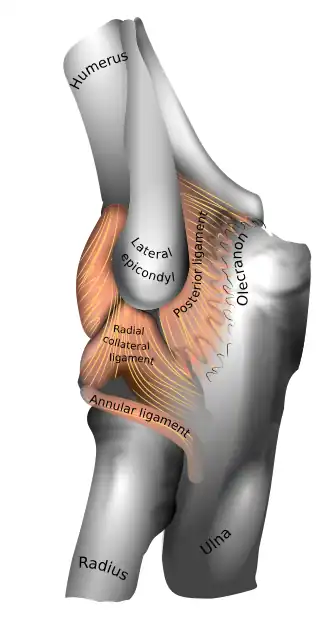

Left elbow-joint, showing anterior and ulnar collateral ligaments.

Left elbow-joint, showing anterior and ulnar collateral ligaments. -

Capsule of elbow-joint (distended). Posterior aspect.

Capsule of elbow-joint (distended). Posterior aspect.